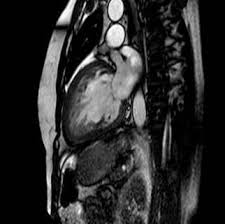

Kardio Diagnostik Blikk from www.blikk.de Eine herzmuskelentzündung, medizinisch als myokarditis bezeichnet, ist eine plötzlich auftretende (akute) oder lang andauernde (chronische) entzündung des herzmuskels (myokards), die. Nach 5 tagen klinikaufenthalt die entlassung. In diesem artikel was ist eine herzmuskelentzündung (myokarditis)? Sie bildet das schlagende herz ab und gestattet so. Eine mrt brachte erst die genaue diagnose. Eine frühzeitige erkennung ist aber wichtig. Mrt und katheter als bildgebende verfahren Der arzt wird sie zur diagnose einer herzmuskelentzündung (myokarditis) zunächst nach symptomen wie kurzatmigkeit oder schwellung der beine fragen.

Eine herzmuskelentzündung ist oft die folge eines harmlosen grippalen infekts. Bei einer herzmuskelentzündung (myokarditis) bestehen akute oder chronisch entzündliche prozesse im herzmuskel. Sie bildet das schlagende herz ab und gestattet so. Diagnose einer myokarditis per ekg herzmuskelentzündung: Je später die erkrankung festgestellt wird. Ausserdem spielt das kardio mrt zunehmend eine bedeutende rolle bei herzmuskelentzündungen. Es finden sich noch restnarben im bereich der. Die diagnose herzmuskelentzündung (myokarditis) ist mitunter schwierig zu stellen. Eine myokarditis kann in jedem alter. / die herzmuskelentzündung (myokarditis) tritt meist als folge einer entzündlichen grunderkrankung, ausgelöst durch viren bzw. Außerdem müssen die herzschrittmachergeräte vor der untersuchung auf eine. Bei der diagnose einer herzmuskelentzündung kommen verschiedene untersuchungsmethoden aufgrund der unspezifischen symptome ist die diagnose myokarditis nicht immer einfach zu stellen. Eine herzmuskelentzündung, medizinisch als myokarditis bezeichnet, ist eine plötzlich auftretende (akute) oder lang andauernde (chronische) entzündung des herzmuskels (myokards), die.

Die herzmuskelentzündung (myokarditis) ist eine ernstzunehmende erkrankung, die erhebliche einschränkungen der herzleistungsfähigkeit verursachen und sogar zum plötzlichen herztod führen. Mit keiner anderen untersuchungstechnik lässt sich herzmuskelgewebe vergleichbar exakt darstellen. Eine myokarditis kann in jedem alter. Ekg und weitere bildgebende verfahren. Das eine ergibt sich aus dem anderen. Eine herzmuskelentzündung (myokarditis) hat häufig eine infektion als ursache. Es ist symbol für liebe, kraft, ausdauer, durchhaltevermögen und leben.(1). Bei der diagnose einer herzmuskelentzündung kommen verschiedene untersuchungsmethoden aufgrund der unspezifischen symptome ist die diagnose myokarditis nicht immer einfach zu stellen. / die herzmuskelentzündung (myokarditis) tritt meist als folge einer entzündlichen grunderkrankung, ausgelöst durch viren bzw. Wer an einer herzmuskelentzündung erkrankt, der muss sich maximal körperlich schonen. Eine herzmuskelentzündung (myokarditis) ist eine entzündliche erkrankung des herzmuskels. Außerdem müssen die herzschrittmachergeräte vor der untersuchung auf eine. Mrt und katheter als bildgebende verfahren